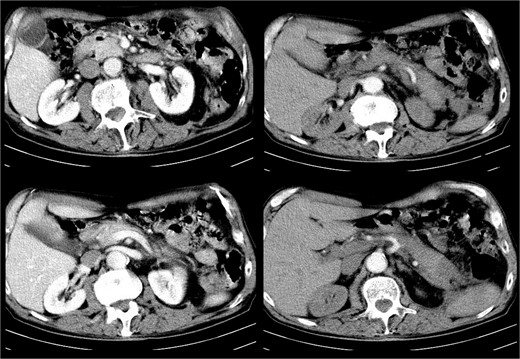

The patient recovered gradually, and no laparotomy was required. A follow-up CT after one month showed no residual collections (Fig. 3).